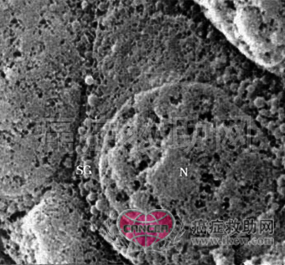

肾上腺肿瘤可由肾上腺皮质的上皮细胞或肾上腺髓质的神经细胞发生。